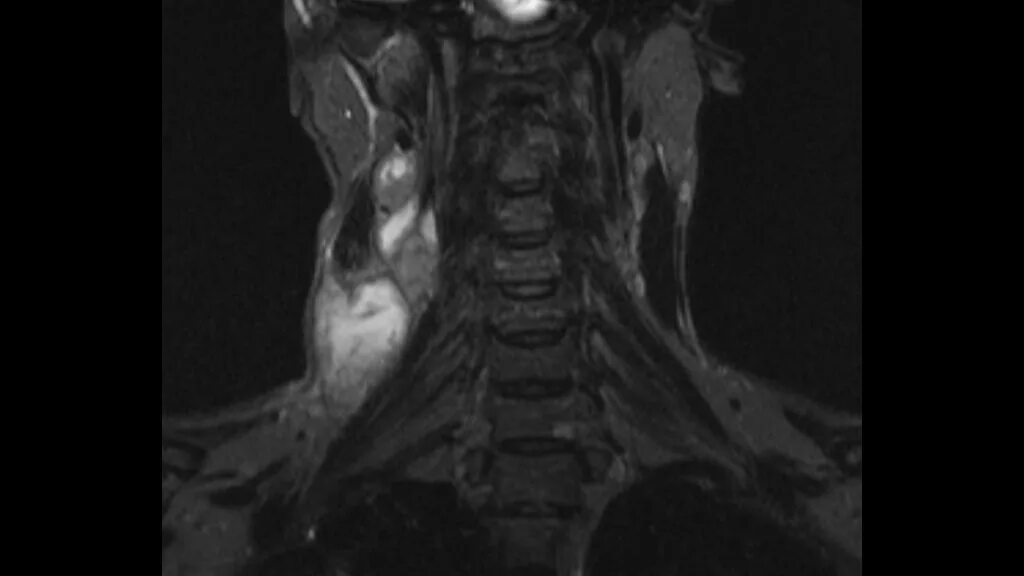

Кт тканей